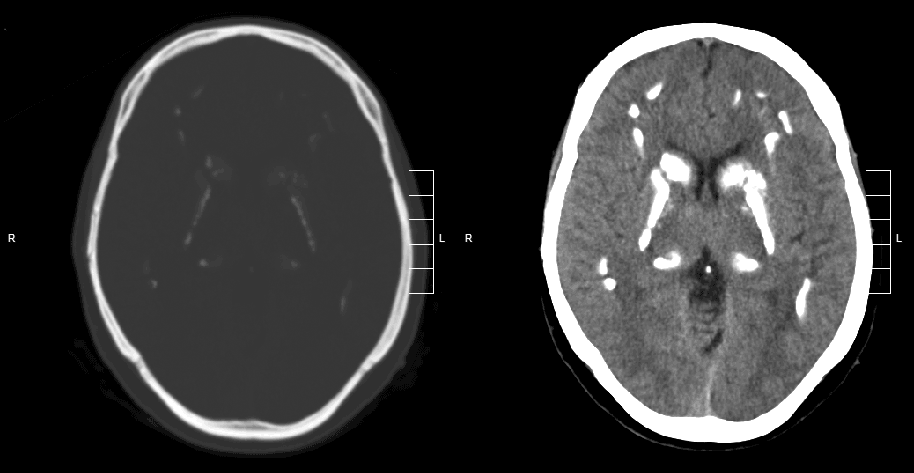

Removal of a cerebral tumor, glioma, Nice Hospital, France. Photo by: BSIP/UIG via Getty Images